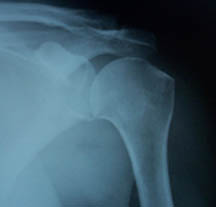

SHOULDER DISLOCATION X-RAYS

Normal